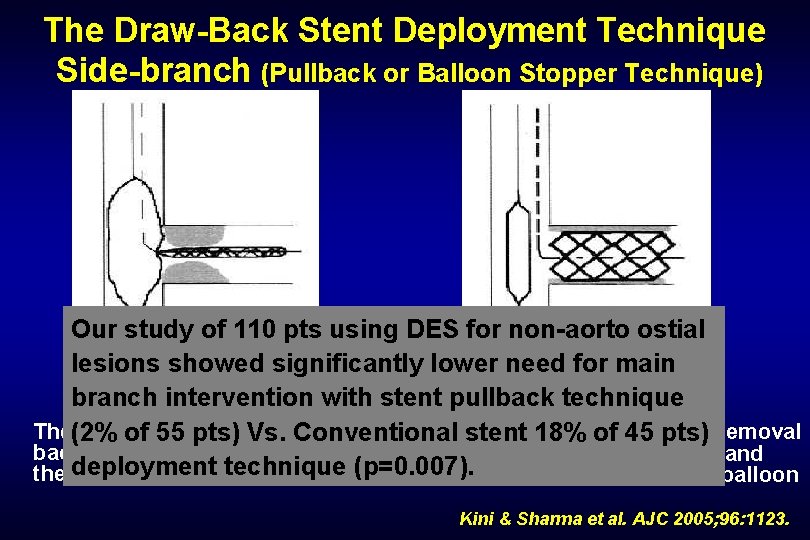

The Draw-Back Stent Deployment Technique Side-branch (Pullback or Balloon Stopper Technique) Our study of 110 pts using DES for non-aorto ostial lesions showed significantly lower need for main branch intervention with stent pullback technique The(2% undeployed stent has. Conventional been drawn. After stent 18% deployment and removal of 55 pts) Vs. stent of 45 pts) back until it comes into contact with of the stent delivery balloon and the deployment inflated balloontechnique in the main(p=0. 007). vesseldeflation of the main vessel balloon Kini & Sharma et al. AJC 2005; 96: 1123.